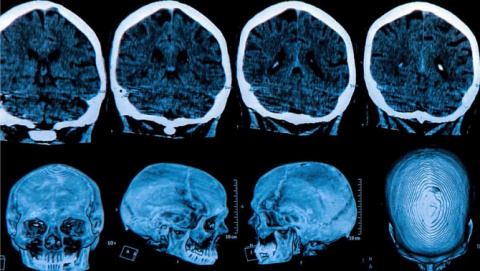

In a study of healthy volunteers, NIH researchers found that taking short breaks, early and often, may help our brains learn new skills. (Credit: Courtesy of Cohen lab, NIH/NINDS)